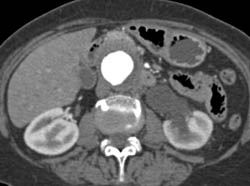

Retroperitoneal Fibrosis With Obstructed Common Bile Duct (CBD) and Left Renal Pelvis- See Full Sequence